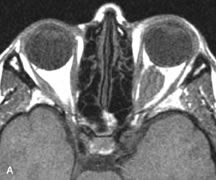

Muscle Disorders

Extraocular muscle enlargement in patients with thyroid-associated orbitopathy is demonstrated equally well with CT and MRI studies. However, the superior tissue contrast on MR images reveals better details of the relationships of the optic nerve to the thickened muscles at the orbital apex (Fig. 16).50 In addition, MRI may be able to differentiate between muscles that are enlarged as a result of edema and active inflammation and those enlarged because of fibrosis by their T2 relaxation times.21 Quantitative MRI was not found to be accurate in predicting the success of low-dose orbital irradiation.51 However, a muscular index relating the diameters of the rectus muscles to the bony orbital dimensions was useful in predicting optic nerve compression.52

Fig. 16. A-C, T1-weighted MR scans obtained with a high-resolution surface coil demonstrate fusiform enlargement of the extraocular muscles. The medial, lateral, and inferior rectus muscles are especially involved. Note the relative sparing of the tendinous insertions, a finding characteristic of this disease process, as well as fatty infiltration of the lateral and inferior rectus muscles. There is marked proptosis, best visualized on the sagittal image (A), and mild crowding of the optic nerve at the orbital apex.